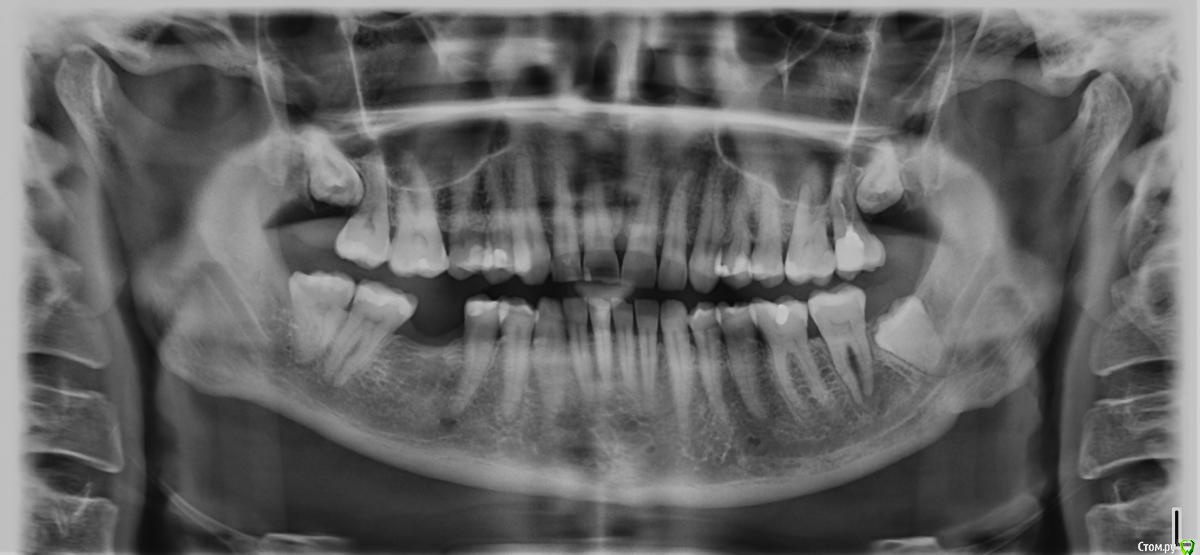

Natalira Опубликовано 15 марта, 2020 Поделиться Опубликовано 15 марта, 2020 (изменено) Здравствуйте,уважаемые стоматологи .помогите разобраться с 26 зубом . В январе 15 года поставили пломбу на жевательную поверхность и закрыли совсем небольшой клиновидный дефект . Зуб заболел через неделю. Врач наносил лак и прописал месяц пить кальций . В 2018 году февраль . Тот же характер болей , но сильней . Я уже в другом городе . Другой врач по сделанному панорамному снимку , ставит диагноз пародонтит( но небольшой как он сказал карман ,совсем маленький ) , чистит карман выписывает антибиотики . Через месяц все проходит . На следующих плановых осмотрах все норм с этим зубом . Январь 2020 заболел 37 зуб, лечение , чистка каналов , абсцесс , удаление ,антибиотики. Через 2 недели после удаления заболел 26.опять чистят карман , через два дня настаиваю на вскрытии каналов ( уже исходя из недавнего опыта с 37 , кот также изначально заболел в 15 году после пломбировки , тогда врач сказал нечему болеть и уже в итоге Переодонтит хронический ). Врач вскрывает каналы , говорит нерв мертв . Придти через 5 дней . Опять чистит каналы ,ставит временную пломбу говорит придти через 10 дней . Прихожу ,говорю что есть ещё боли,но не всегда и незначительные . Прошу поменять лекарство , говорит что в моем случае нет необходимости . Я говорю что переживаю ,что хронический Переодонтит был 4 года . Врач уверено говорит что будет пломбировать каналы и пломьирует , делает снимки ( 4 раза переснимал),говорит что все хорошо. И что приходить через месяц перелечивать 27 зуб . Но он не болел ни разу , несмотря на плохо запломбированный каналы ( врач сказал по снимку) и он так уже минимум 20 лет . Изначально 26 и 37 начинала лечить в России. ССейчас лечу по месту жительства . Программный снимок так же есть до удаления 37 зуба . В 26 временами возникают неприятные ощущения . Боль в районе корня стихает . Врач сказал ,что со временем пройдет . Извините за ошибки ,пишу с телефона . PS: КТ было сделано с временной пломбой , до пломбировки каналов гуттаперчей Изменено 15 марта, 2020 пользователем Natalira Ссылка на комментарий

Natalira Опубликовано 16 марта, 2020 Автор Поделиться Опубликовано 16 марта, 2020 (изменено) И как часто можно делать КТ? У у нас даже не одевают защитный фартук , ни для панорамного снимка ни для КТ.внутриротовые снимки врач делал 4 штуки после финальной пломбировки .сказал что все нормально запломбированы . Но они у него .на мои жалобы на брль в области корня зуба , сказал что со временем пройдет . На панорамном снимке он увидел что между 26 и 27 что когда то был абссец в районе черного пятна . Я не знаю как это понимать . 2 года назад ,он болел , но другой врач ничего не нашел по панорамномному снимку ,2 годичной давности тоже снимок есть . За 2 месяца я уже просто морально и физически устала и от болевых ощущений и от моральных . Изменено 16 марта, 2020 пользователем Natalira Ссылка на комментарий

Natalira Опубликовано 16 марта, 2020 Автор Поделиться Опубликовано 16 марта, 2020 (изменено) Это уже третий врач .но 26 лечил один врач Не все так просто у нас с врачами. Поэтому Пишу с надеждой на помощь на форуме.Снимки он мне не дал на руки. Многие просто отказываются даже смотреть КТ. Панорамный делала 28 января , через месяц КТ. Как часто можно делать такие обследования ? Но хотябы из моих снимков что с 26 зубом был периодонтит или просто пульпит ? Очень надеюсь на консультацию . Изменено 16 марта, 2020 пользователем Natalira Ссылка на комментарий